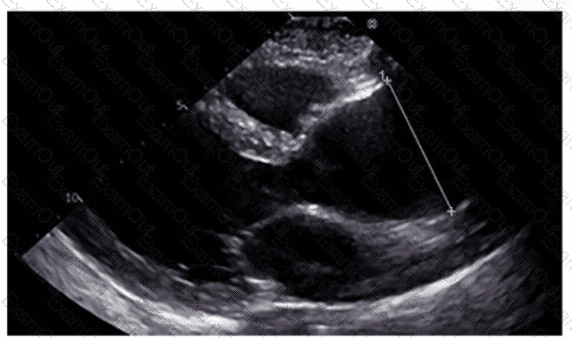

Which method is appropriate for measuring the left atrial diameter in parasternal long axis?

Which region of the aorta is being measured to assess the critical finding in this image?